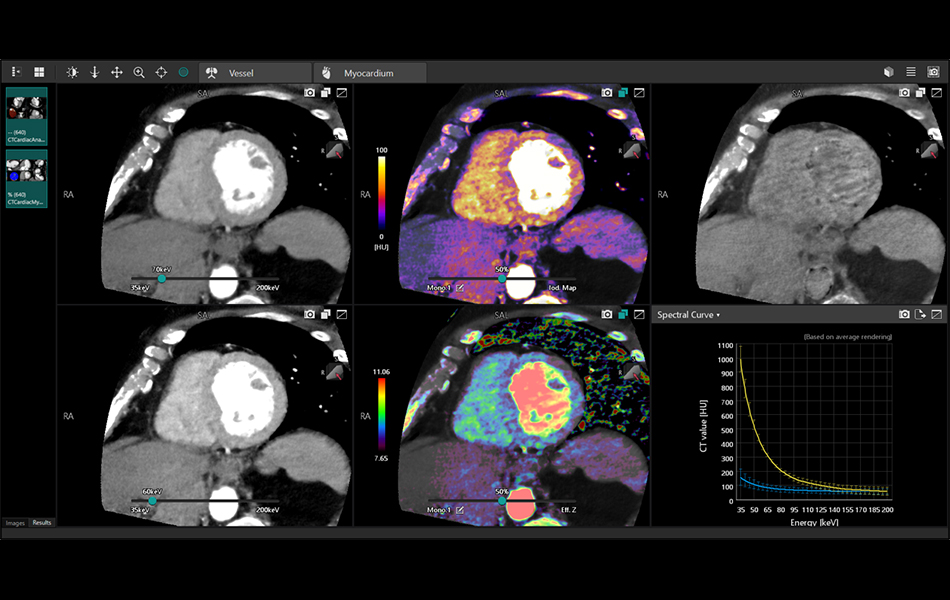

Spectral Cardiac Analysis (7.15.6)

Allows the user to review ECG gated spectral cardiac imaging to visualize and quantify iodine distribution, assess electron density and effectiveZ values within the myocardium and coronary arteries. Extraction of the myocardium and coronary arteries are supported by Vitrea’s industry leading myocardium (Myocardial Perfusion) and coronary artery analysis (Cardiac Analysis) applications. Spectral Analysis can inherit these extraction results.